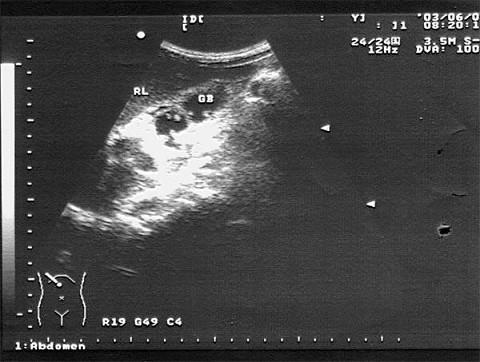

问题 男,56岁,上腹经常疼痛不适多年。结合超声声像图,诊断为?(?)

选项 A.胆囊多发性胆固醇结晶 B.胆囊多发性息肉 C.胆囊多发性结石 D.胆囊癌 E.胆泥淤积

答案 B